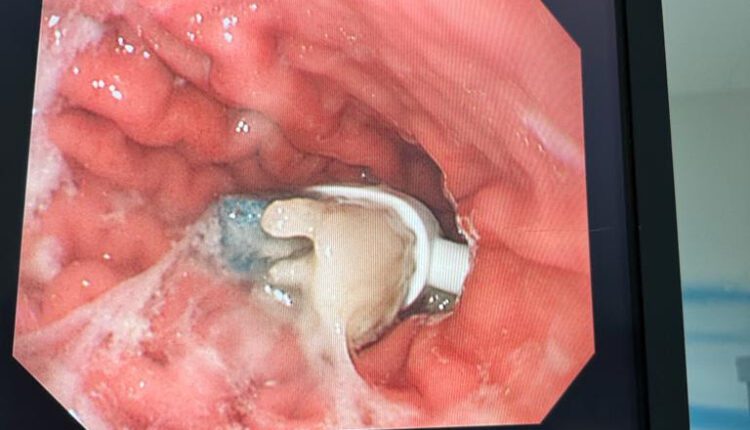

نجح فريق طبي في مستشفى الولادة والأطفال بمكة المكرمة الأحد 25 ديسمبر في استخراج فرشاة أسنان من معدة طفل يبلغ عمره 9 سنوات وذلك بالمنظار من دون تدخل جراحي.

وقال التجمع الصحي بمكة المكرمة أنه تم نقل الطفل إلى طوارئ المستشفى نتيجة ابتلاعه رأس فرشاة الأسنان الكهربائية. وبعد عمل الفحوصات الأولية وإجراء الأشعة السينية لمعرفة مكان الفرشاة داخل الجهاز الهضمي تم تحديد مكانها بدقة داخل المعدة، حيث قرر الفريق الطبي المعالج إزالتها حتى لا تؤدي إلى انسداد معوي.

وقد تم إجراء العملية بواسطة المنظار خلال مدة 20 دقيقة دون أية مضاعفات، ويواصل ابن التاسعة قضاء فترة النقاهة بالمستشفى تحت الملاحظة الطبية.